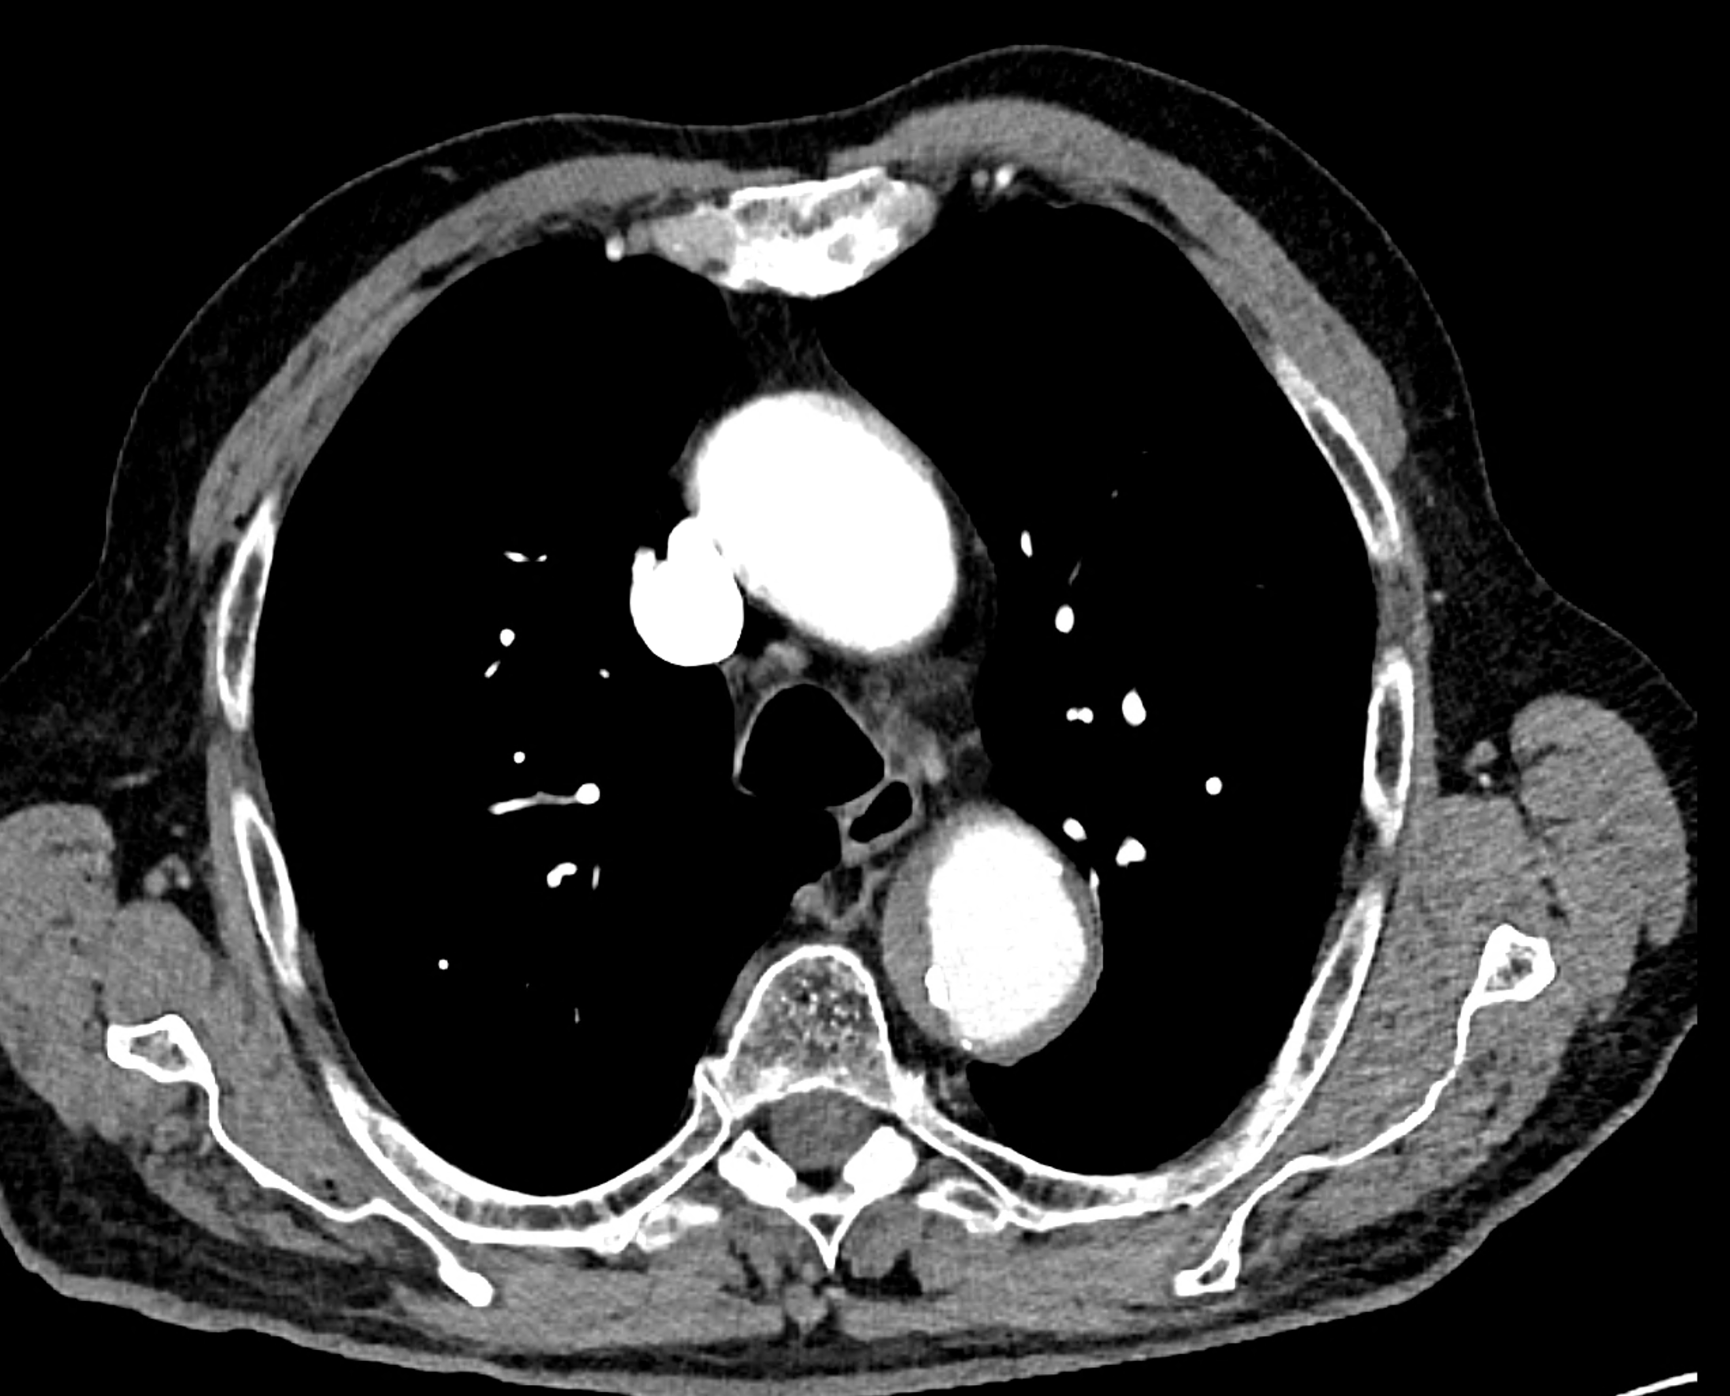

in patient chest pain, negative ECG but with elevated D-dimers was performed CTA of the chest to exclude highly suspected pulmonary embolism. No pulmonary embolism was see, but the pathology of the aortic arch and descending thoracic atorta. The images were consistent with aortic intramural hematoma type B according to the Stanford classification with incipient transformation in dissection – behind the subclavian artery, it is clear that the contrast agent is flowing into the intramural hematoma. Differentiation from wall thrombosis is facilitated by the presence of calcification in the detached intima, which is most clearly visible on virtual non-contrast imaging. The intramural hematoma itself exhibits different properties in terms of X-ray absorption. Coagulated blood is visible at the apex of the aortic arch, where it closely adjoins the area that is perfused and filled with contrast medium. There are other smaller areas filled with contrast medium at the sites of the intercostal arteries. These areas are secondary sites where the original intramural hematoma is channeled during its transformation into a classic aortic dissection.

Virtual non-contrast images help to distinguish between the intima and thus in the differential diagnosis of intramural hematoma versus wall thrombosis. Signs of fresh coagulated blood in IMH indicate bleeding into the aortic wall from the vasa vasorum. In contrast, monoenergetic images with lower energies of 40-55 keV highlight areas of intramural hematoma with active blood flow.

comparison of the the images 60, keV monoenergetic, virtual non-contrast (VNC), and iodine map images. The repercussion starts in the proximal tear of the intimate (the first three images), calcification in the intimate (next three images), tera at the level of the arising intercostal artery (last three images)

comparison of the sagittal aortic MPR in 40, 60, 140 and 190 keV monoenergetic images

comparison of the perpendicular planes to sagittal aortic MPR in 40, 60, 140 and 190 keV monoenergetic images